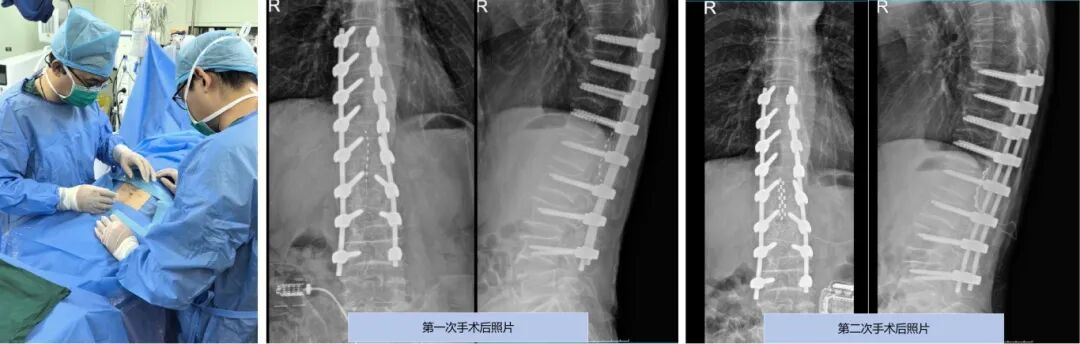

为确保最佳疗效,手术分两阶段进行。首先,程黎明通过微创穿刺,为谭先生植入了临时脊髓电刺激电极。在为期一周的体外测试中,谭先生的疼痛得到了显著缓解,这预示着永久植入将能取得良好效果,也极大地增强了他的治疗信心。

三周后,程黎明团队为谭先生成功实施了第二阶段手术,植入永久性的脊髓电刺激装置。手术在全麻下完成,由于患者在美国完成的减压手术,其术后神经与周围组织是否存在粘连,以及粘连的位置与程度,通过现有的影像资料均难以准确评估。这些不确定性给永久电极的植入增加了不小的难度。为此,程黎明在术前制定了多个手术备选方案。在手术中,他仔细探查并分离硬脊膜周围的粘连,在麻醉科、手术室的配合下,按预定计划顺利置入了永久电刺激电极,并将刺激器放置在预定的腹部肌肉表面。术后,根据谭先生的个体感受,精细调整了刺激参数。最终,折磨他一年多的疼痛减轻了90%以上。

▲程黎明教授为患者实施手术